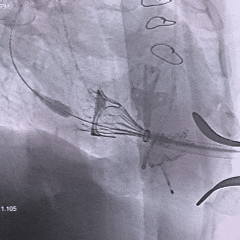

术中影像

右侧垫肩,基本打平原外科瓣瓣架,工作体位:RAO29° CRA12°

直头导丝顺利跨瓣

Mark点平齐外科瓣瓣架低端进行定位

瓣膜全展开位可见同轴稍差,心房内上浅下深

瓣膜回收后,旋转输送器弯型调整同轴

瓣膜重新释放至全展开位,可见位置合适,流出端可见形态压缩

超声评估瓣膜位置可,无瓣周漏

瓣膜稳定脱钩

28mm球囊后扩,瓣膜形态明显改善

最终评估可见瓣膜形态、位置均理想